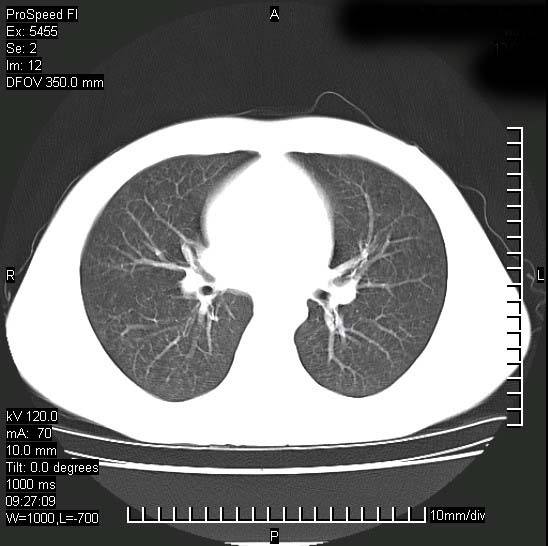

以下是引用zjzjr在2008-12-3 20:50:00的发言:[br]考虑泛细支气管肺炎,建议进一步检查除外肺出血性疾病如含铁血黄素沉着症、肺肾综合征等。

以下是引用zjzjr在2008-12-3 20:50:00的发言:[br]考虑泛细支气管肺炎,建议进一步检查除外肺出血性疾病如含铁血黄素沉着症、肺肾综合征等。

以下是引用光线在2008-12-3 20:19:00的发言:[br]双肺间质性改变。